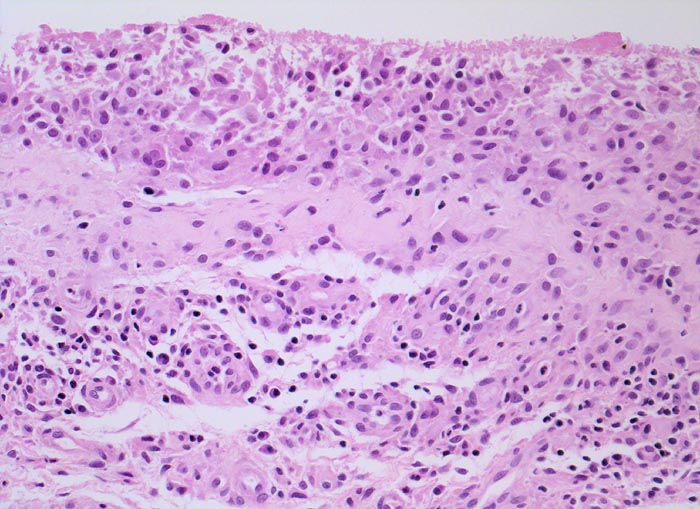

Typische histologische Veränderungen sind eine synoviale Zottenhyperplasie, Verbreiterung der Deckzellschicht unter Einschluss mehrkerniger Riesenzellen, Fibrinexsudate und synoviale Ulzerationen, Infiltrate von Lymphozyten teils in Form von Lymphfollikeln, Plasmazellen, neutrophilen Granulozyten, Makrophagen und Siderophagen, sowie Einschlüsse von Knorpel- und Knochenfragmenten (Detritussynovialitis). Die histologischen Befunde der Synovialis korrelieren oft nicht mit den klinischen Angaben. Trotz fortgeschrittener Gelenkdestruktion mit ausgeprägter klinischer Symptomatik können Synovialektomiepräparate nur sehr geringe pathologische Veränderungen zeigen. Oft ist auch nicht mehr zu eruieren, welche Läsionen Folge der Grundkrankheit und welche Folge diverser intraartikulärer Therapien oder begleitender Superinfektionen sind.

Bei einem grösseren Teil der Gelenkerkrankungen ist die histopathologische Diagnostik dadurch eingeschränkt, dass nur uncharakteristische Befunde zu erheben sind. Um die Synovialitisdiagnostik zu standardisieren, wurde ein Gradierungssystem, der sog. Synovialitis-Score, vorgeschlagen. Gradiert werden die Dicke der Deckzellschicht, die Zelldichte des synovialen Stromas und das chronische Entzündungsinfiltrat. (0-1 Punkt: keine Synovialitis; 2-4 Punkte: low-grade Synovialitis; 5-9 Punkte: high-grade Synovialitis). Der Befund einer hochgradigen Synovialitis als diagnostisches Kriterium für eine rheumatische Erkrankung besitzt eine Sensitivität von 60.5% und eine Spezifität von 95.5%. Die diagnostische Synovialisbiopsie bleibt aber ausgewählten und klinisch unklaren Konstellationen vorbehalten und ist in der Mehrzahl der Fälle nicht erforderlich.

• Stark proliferierte mehrreihige synoviale Deckzellschicht.

• Herdförmig Fibrinauflagerungen durchsetzt von neutrophilen Granulozyten.

• Hyperzelluläres Stroma mit lymphoplasmazellulärem Entzündungsinfiltrat mit Ausbildung von Lymphfollikeln.